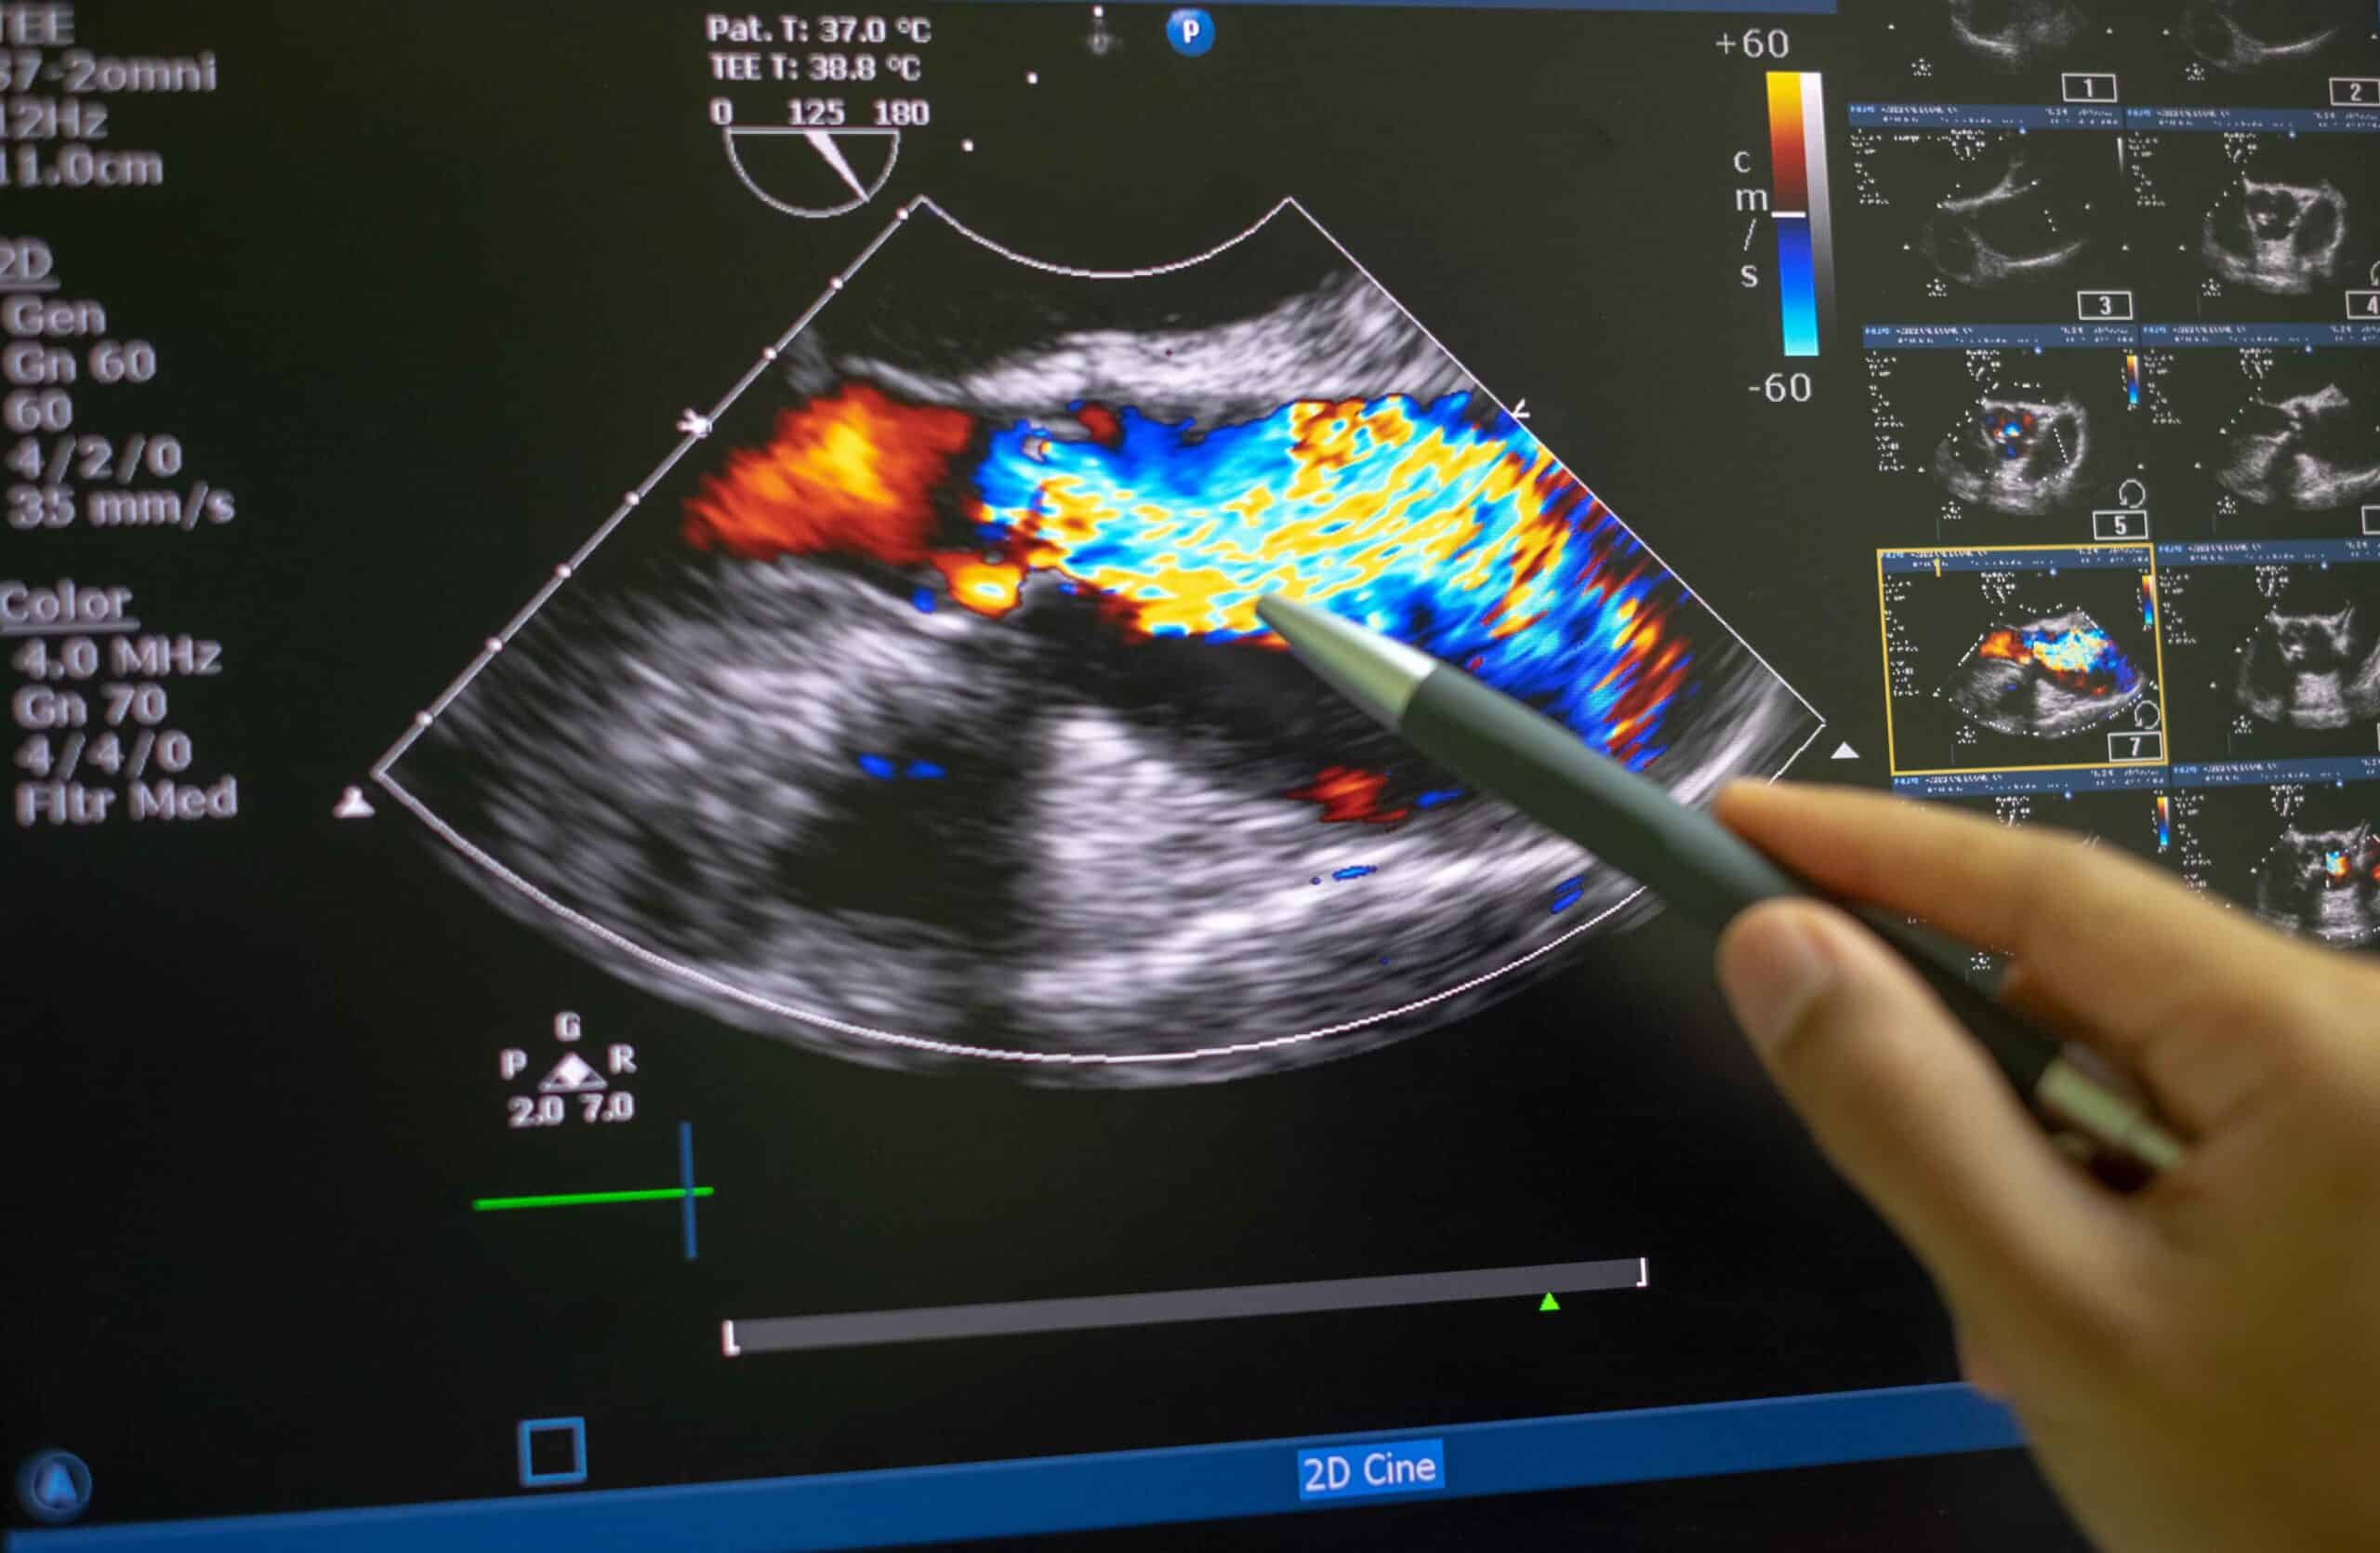

Echocardiograms (Heart Ultrasound)

When a pet has a heart murmur or signs of cardiac disease (like coughing, lethargy, or exercise intolerance), an echocardiogram provides a closer look at how the heart is functioning.

We use echocardiograms to:

Results from these tests help us determine whether your pet needs medications, further testing, or specialist care.